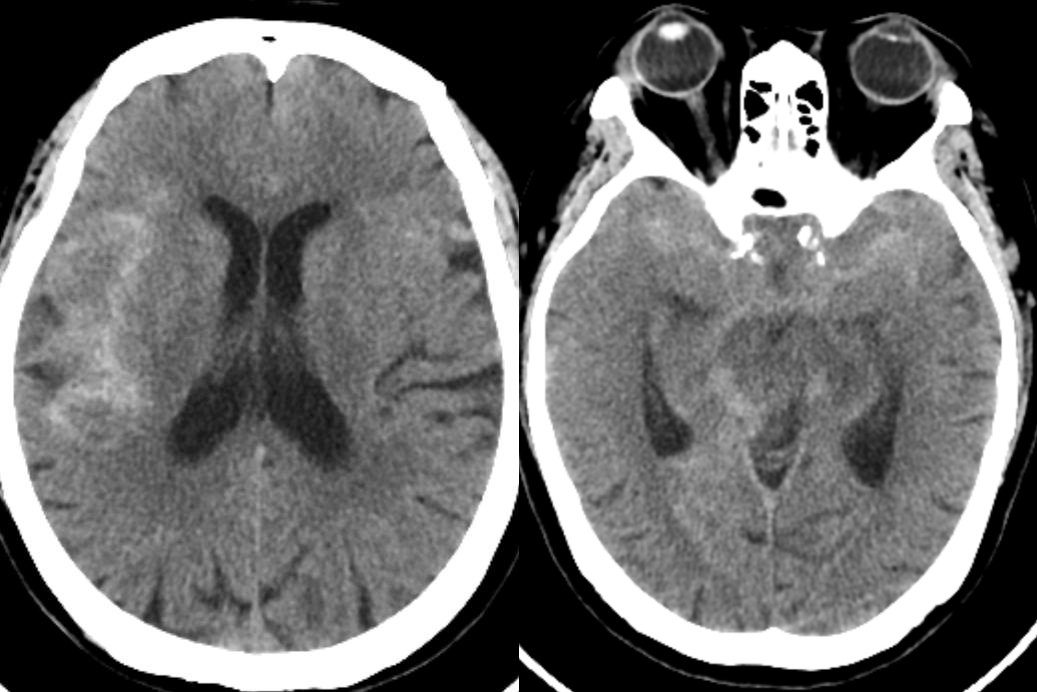

今年已是“米寿之年”的患者李女士有30余年高血压和8年冠心病史,平素生活可自理。入院前3天突发剧烈头痛,伴恶心,未及时就医诊治。9月1日清晨,她突发头痛并加重,前往清华大学附属垂杨柳医院急诊就诊,头颅CT提示蛛网膜下腔出血。请神经外科会诊并进行了科内专家组讨论,结合头颈动脉CTA检查,认为李女士为颅内动脉瘤破裂伴蛛网膜下腔出血。

▲头颅CT显示蛛网膜下腔出血,右侧偏多